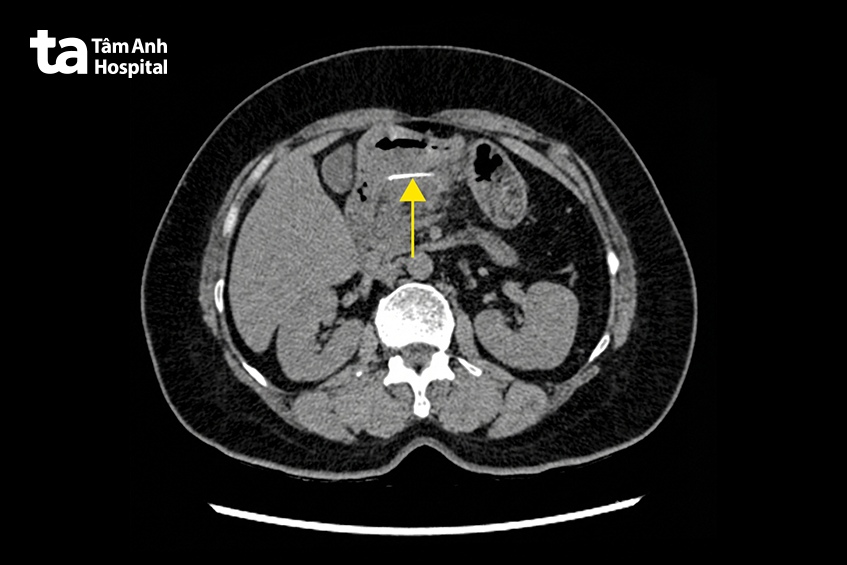

Tại bệnh viện, các bác sĩ chỉ định chụp CT đa lát cắt (1975 lát cắt). Kết quả ghi nhận một dị vật dạng đường dài khoảng 3 cm, mảnh, nằm ở hậu cung mạc nối, sát thành môn vị dạ dày tạo thành khối áp xe.

Thạc sĩ bác sĩ Võ Nhật Trường – Trung tâm Nội soi và Phẫu thuật Nội soi Tiêu hóa, Bệnh viện Đa khoa Tâm Anh TP HCM, cho biết dị vật đã đâm xuyên toàn bộ thành dạ dày, tạo thành khối viêm nhiễm áp xe ở hậu cung mạc nối. Đây là nguyên nhân khiến bệnh nhân đau bụng dữ dội, nôn ói, không ăn uống được.